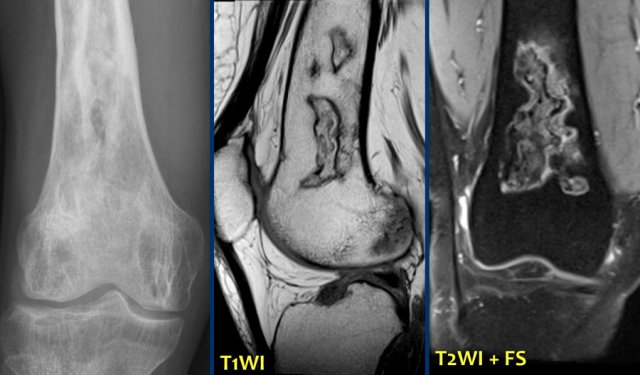

ABC (8)

On the left another ABC, located in the distal femur.

The plain radiograph shows a layered periosteal reaction and Codman triangle in direct relationship to an expansile lytic lesion with a thin peripheral bone shell.

CT also reveals the subperiosteal origin of the lesion with secondary involvement of the cortical bone.

Axial T2-weighted image with fatsat and contrast enhanced T1-weighted image with fat sat show multiple fluid-fluid levels with rim enhancement of the cavities filled with blood.

This is typical for an aneurysmal bone cyst.